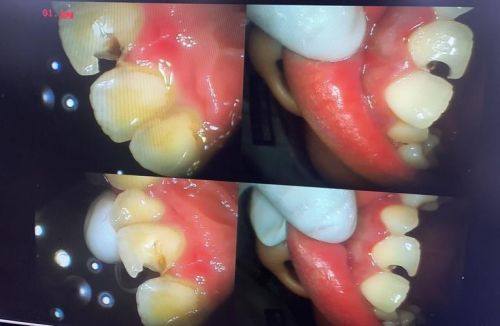

补牙:针对中龋、深龋等不同程度的牙体缺损,选用合适的修复材料,补牙后牙齿形态自然贴合,能良好修复牙齿的咀嚼功能,且耐用性强。

全冠牙修复:针对重度牙体缺损或根管治疗后的牙齿,进行全冠牙修复,修复后的牙齿形态逼真,功能完善,能长期维持口腔健康。